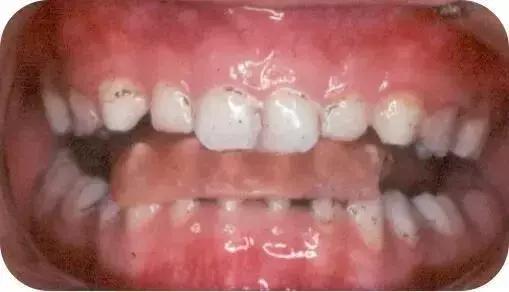

07

前方牵引

没得错,这也是一个让你长期戴的矫治器。

成人矫正案例一

成人矫正案例二